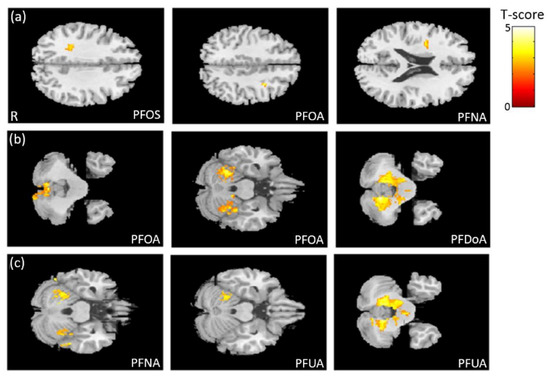

3.3. The Association between PFCs and VBM

3.5. The Association between Phthalate Esters and GQI